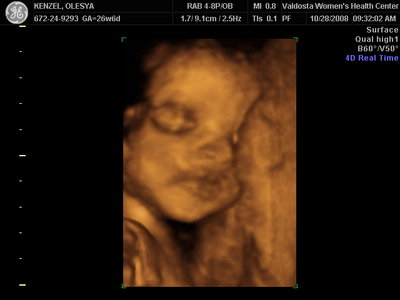

Еще одна Джианнка:

| Вложения: |

KENZEL,OLESYA_5.JPG [ 60.02 КБ | Просмотров: 1513 ]